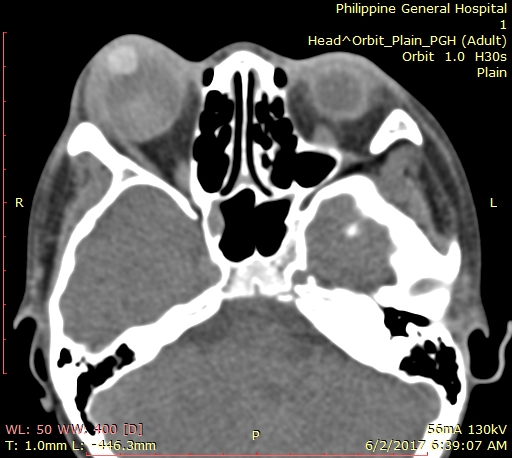

In the interim, the patient was lost to follow-up, but returned 20 days after, when it was noted that there was recurrence of total hyphema, with staining of the corneal graft, shown in Figure 3 [Fig. 3]. Visual acuity returned to light perception, extraocular muscle movements decreased to 2/4. As seen in Figure 4 [Fig. 4], there was extensive thinning of the sclera, bloody chemosis, and proptosis. Computerized tomography scan of the orbit (Figure 5 [Fig. 5]) was done and showed the proptosed right globe, with peribulbar radiopaque densities, possibly new/fresh hemorrhage. Ocular ultrasound showed development of vitreous hemorrhage, with peripheral retinal detachment but a normal axial length.

Figure 5: Third-week postoperative orbital computerized tomography scan